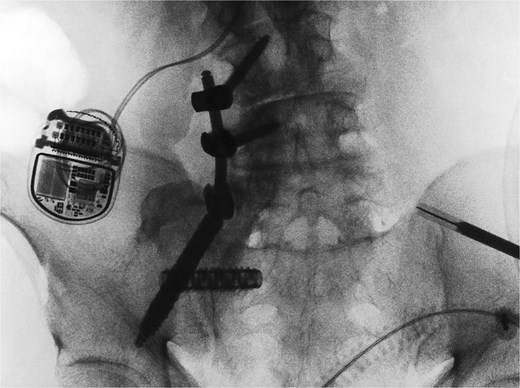

Next, a minimally invasive right SI joint bolt was placed. A second, 1-in. incision was made over the right lateral iliac fossa. A navigated drill was used to cannulate a pilot hole through the right ilium, crossing the sacroiliac joint, into the right sacral ala. A 12 mm tap was then used, and a 12 mm diameter, 50 mm length Rialto SI joint fusion implant was inserted across the right sacroiliac joint. A final O-arm scan was performed to confirm good position of all implants (Fig. 3).

Intraoperative O-arm spin confirmed placement of the right L4 and L5 pedicle screws, as well as the right iliac screw and right sacroiliac implant. The left-sided navigation clamp can be visualized. The patient’s spinal cord stimulator (seen in the figure) was carefully avoided. One can also see the pronounced osseous abnormality along the right lower spine, extending to the sacrum and medial ilium.